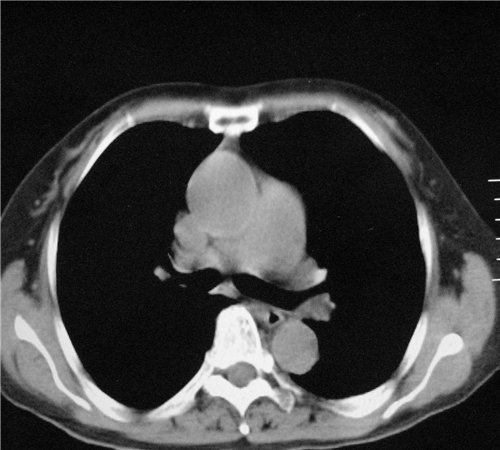

标题: CT26849:女67岁反复胸痛两天余,临床考虑夹层。 [打印本页]

标题: CT26849:女67岁反复胸痛两天余,临床考虑夹层。

右肺感染,未见夹层。

未见夹层

既然考虑夹层,建议强化!另:右下肺感染!

1)右肺感染性病变。2)建议行ct增强扫描或mri检查排除主动脉夹层。

双下肺感染,右侧显著。有无夹层,增强扫描后再诊断。

1. 感染性病变,2.未见夹层,3.食道未见异常。

平扫未见确切夹层征,建议必要时增强扫描或mri检查。